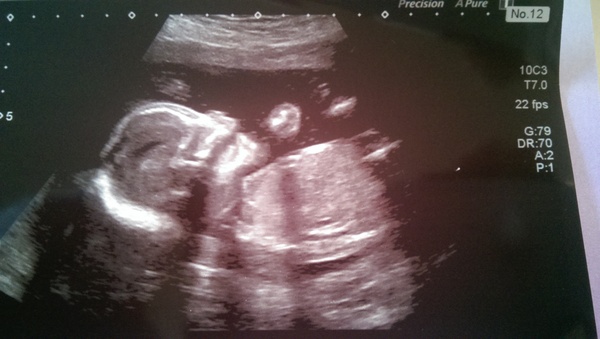

bradders85 · 04/12/2014 17:00

This is one of todays scan photo's - we are having a surprise but am happy to guess and speculate so any guesses welcome! I'd say boy?!

Aww lovely clear picture bradders. Must have been lovely seeing baby again! I'm definitely finding out the sex- far too impatient to wait! For those who have had babies already, how accurate was your intuition over what you're having? I think I'm having boy for some reason and feel quite convinced! Will find out on Dec 29th!

Thanks blondie it was great to see baby again and I will get the chance again in a few weeks as they couldn't get all measurements (quite pleased really!) - and relieved obviously that what they could see was all ok. I having had any intuition but dp has been convinced from the start its a boy! Bet you can't wait to find out and a nice treat for you before new year!

Congratulations Bradders, I think that's a girl!

oohh interesting turquoise I like the guessing game and getting different opinions! And congrats snooky on a little girl :) Pleased everything went ok x

bradders lovely scan pic! :)

Lovely clear scan pic Bradders, I say that's a boy!

Congrats bradders, I think boy :)